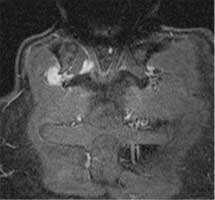

Der lumbale Sympathikus besteht aus drei bis vier Nervenganglienpaaren, die an der Vorderkante der Wirbelkörper rechts und links der großen Gefäße und des beiderseitigen Musculus psoas im Fettgewebe liegen. Die Rami communicantes verbinden die Ganglien strickleiterartig sowohl nach kranio-kaudal als auch von links nach rechts. Eine weitere Umschaltung erfolgt über die Rami albi, die durch die Neuroforamina neben den Segmentnerven zum Duralsack verlaufen und dann im Rückenmark weitergeleitet werden. Bei umschriebenen peripheren arteriellen Verschlüssen kann bei der Sympathikolyse mit einer hohen Erfolgsrate (ca. 75%) gerechnet werden. Der beste Effekt lässt sich in Kombination mit einem intensiven Gehtraining erzielen. Als gute Indikationen zur lumbalen Sympathikolyse zählen Verschlüsse der Unterschenkel- und Fußarterien auch bei kombinierten Oberschenkelverschlüssen. Trophische periphere Ulcera sind durch die lumbale Sympathektomie ebenso wie Nekrosen der Zehen zu behandeln. Bei ca. 45 Prozent der Patienten mit Stadium IV können sich die Nekrosen vollständig zurückbilden. Patienten mit Diabetes mellitus zeigen in der Regel ein schlechteres Ansprechen. Die lumbale Sympathikolyse ist durch die CT-Kontrolle heute zu einer Standard-therapie bei der Behandlung von peripheren arteriellen Durchblutungsstörungen geworden. Die beste Indikation ist im Stadium III nach Fontaine gegeben, aber auch im Stadium IIb kann bei schlechter Ausstrombahn in Kombination mit gefäßchirurgischen Eingriffen oder einer Angioplastie eine Indikation vorliegen. Die Nebenwirkungen sind wegen der hohen Präzision der CT-Steuerung gering. Da die Behandlung unter Lokalanästhesie durchgeführt wird, kann in vielen Fällen eine ambulante Therapie erfolgen. In Bauchlage werden nach Gabe von 1 ml Kontrastmittel pro Kilogramm Körpergewicht die Ureteren kontrastreich in der Ausscheidungsphase dargestellt. Nach Lokalisation der sympathischen Ganglien durch eine Spiral-CT des Mittel- und Unterbauches werden die Einstichstellen an der Haut bestimmt und markiert. Nach Lokalanästhesie der Haut und der autochthonen Rückenmuskulatur wird eine 22 G Shiba-Nadel durch den Musculus psoas zu den jeweiligen Ganglien unter lokaler Anästhesie vorgeschoben (Abbildung). Etwa 0,5 ml Kontrastmittel wird zur Prüfung der Verteilung am Sympathikus injiziert. Zur Ausschaltung des Sympathikus sind bei exakter Positionierung der Nadelspitze ca. 5 bis 10 ml 95%igen Alkohols erforderlich.

![]() |